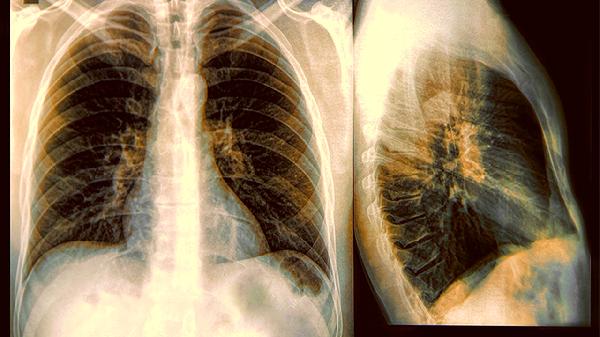

明明烟盒都没摸过,体检单上却赫然写着"肺部磨玻璃结节"?最.近几年,越来越多不吸烟的女性被肺癌找上门,连医生都在纳闷:传统认知里的"老烟枪专属病",怎么悄悄换了目标人群?